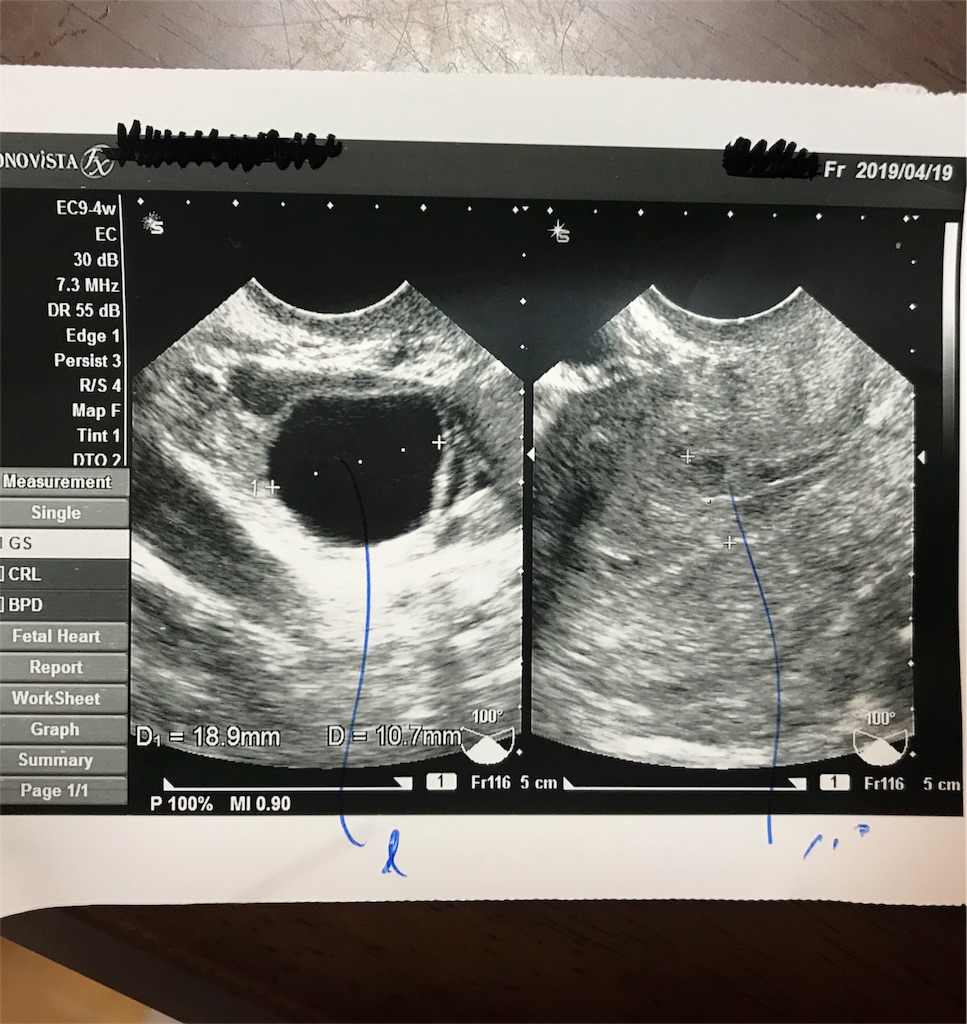

レディースクリニック受診日 超音波検査(主人同席)

右:18.9mm 左:10.7mm

子宮内膜:1.0mm

先生「しっかり大きくなってるね。もうすぐ排卵しそうだね」

先生「それはあんまり関係ないですね。排卵は月曜日辺りですね。明日と月曜日の2回関係を持ってもらえますか?ご主人、大変だけど頑張ってください笑笑」「今回は自然に排卵するのを待ちましょう。月曜日に排卵しているはずなので、火曜日辺りに来てください」